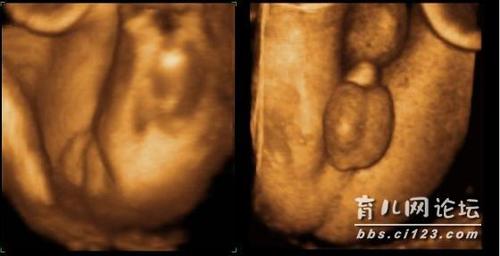

这是我在别的论坛上看到的帖子,分别是女宝和男宝的四维

四维男女宝宝区别图

四维胎儿性别器官图片